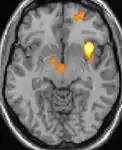

| Positron emission tomography (PET) shows brain areas being activated during pain. | ||

Positron emission tomography (PET) scans indicate the brain areas which are activated during attack only, compared to pain free periods. These pictures show brain areas that are active during pain in yellow/orange color (called "pain matrix"). The area in the center (in all three views) is specifically activated during CH only. The bottom row voxel-based morphometry (VBM) shows structural brain differences between individuals with and without CH; only a portion of the hypothalamus is different.[36]